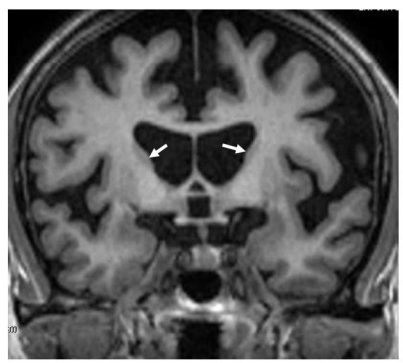

Huntington’s Disease

Loss of volume of Caudate Nucleo, enlargement of frontal horns

Enlargement of subarachnoid space, frontal convexity, interhemispheric scissure, sylvian region, and choroid fissures